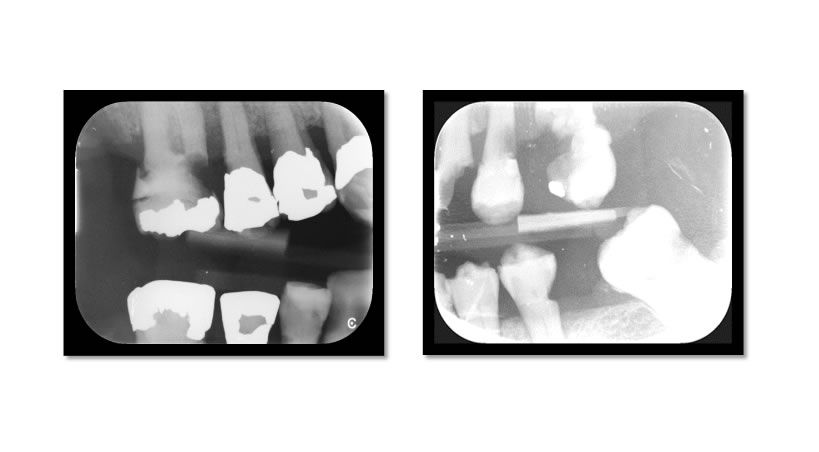

Relación entre la Periodontitis Crónica y la Aterosclerosis

Descripción de los mecanismos de asociación entre estas dos patologías. Revisión de la literatura.